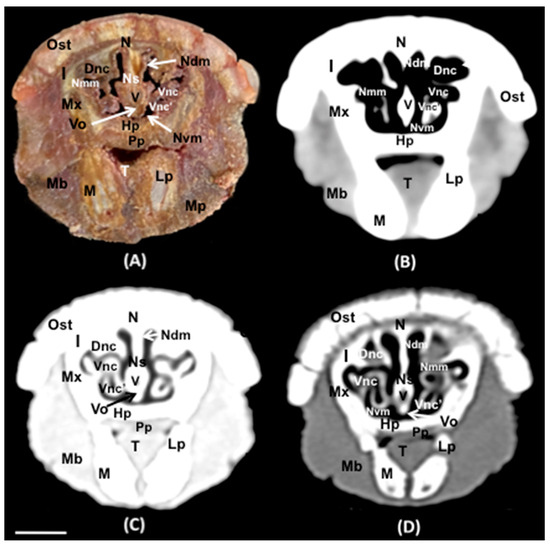

3.1. Anatomical Sections

3.2. Computed Tomography (CT)